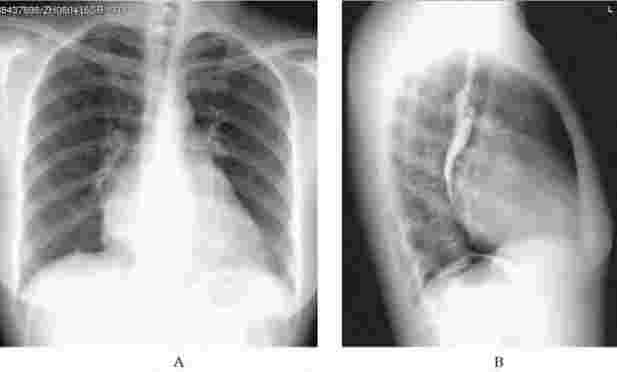

单纯二尖瓣狭窄继发左房增大、肺淤血、肺水肿;长期肺淤血肺循环阻力增高导致肺动脉高压,肺动脉段突出、右室大。左室充盈减少可缩小,主动脉结也缩小(图5-17)。伴有二尖瓣关闭不全时,左室负担加重可肥厚增大(图5-18)。

图5-17 二尖瓣狭窄X线表现

A.正位;B.侧位。左房增大,表现为心脏后上方偏左侧增大,正位像可见心影中的高密度部分(双重密度影),侧位像可见食管在左房水平受压后移。另一表现为肺血再分布,表现为肺上静脉增粗,肺下静脉痉挛变细